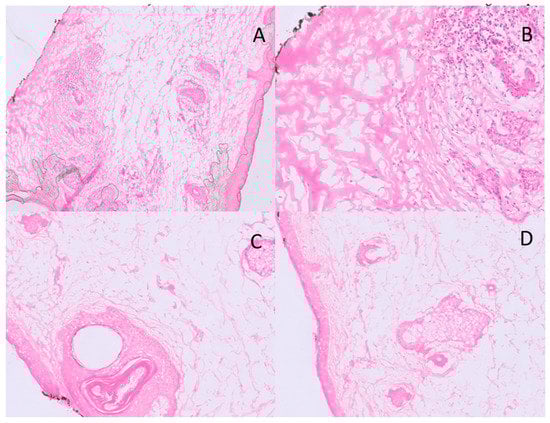

After each margin evaluation, the pathologist called the surgeon in the operating room by phone to communicate the diagnosis. A second sample was taken from the area where residual tumor was visible when a sample was found to have tumor cells after histopathologic analysis. Until clean margins were achieved, fresh tissue from the excision was delivered to the pathology laboratory. Only when the histopathological analysis no longer found tumor cells in any margin the oculoplastic surgeon could perform the reconstruction (Figure 3). The diagnosis of the frozen slices was then confirmed by sending all samples for long-term paraffin sections. Through this mixed approach, precise microscopic control of all margins can be achieved with more effective preservation of normal tissue and reduced sacrifice of healthy tissue.

Figure 3. An example of BCC positive margin at low (A) and high (B) power magnification (H&E); in the hypodermis, small nests of BCC are visible, closely related to an inflammatory focus. An example of BCC negative margin at low- (C) and high-power (D) magnification (40×).